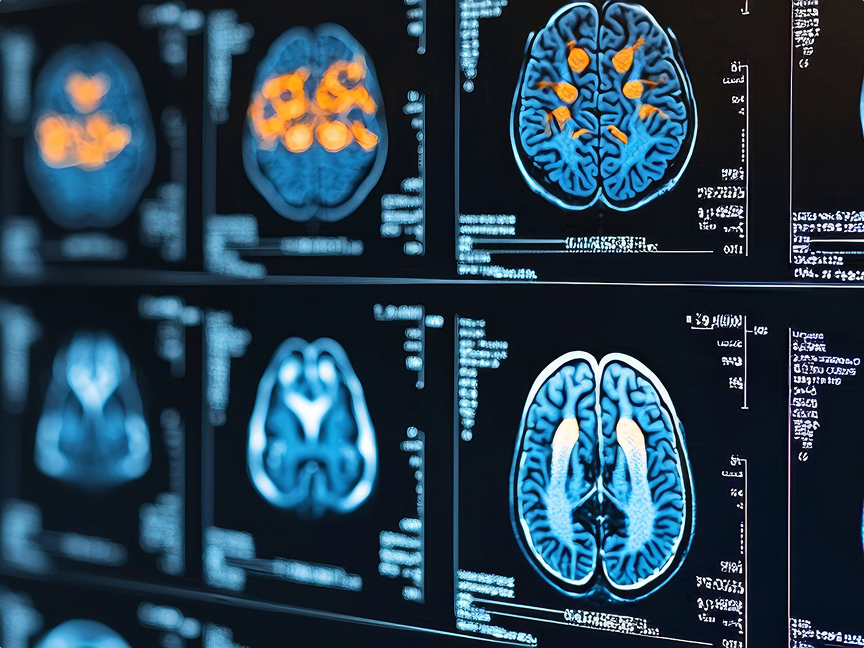

- The physician uses MRI images to view and assess the treatment area.